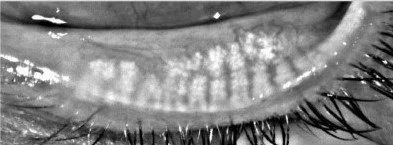

Meibomian gland after treatment. Optometry. Eye specialist. Eye treatments in vancouver.

Meibomian Gland atrophy after Accutane use